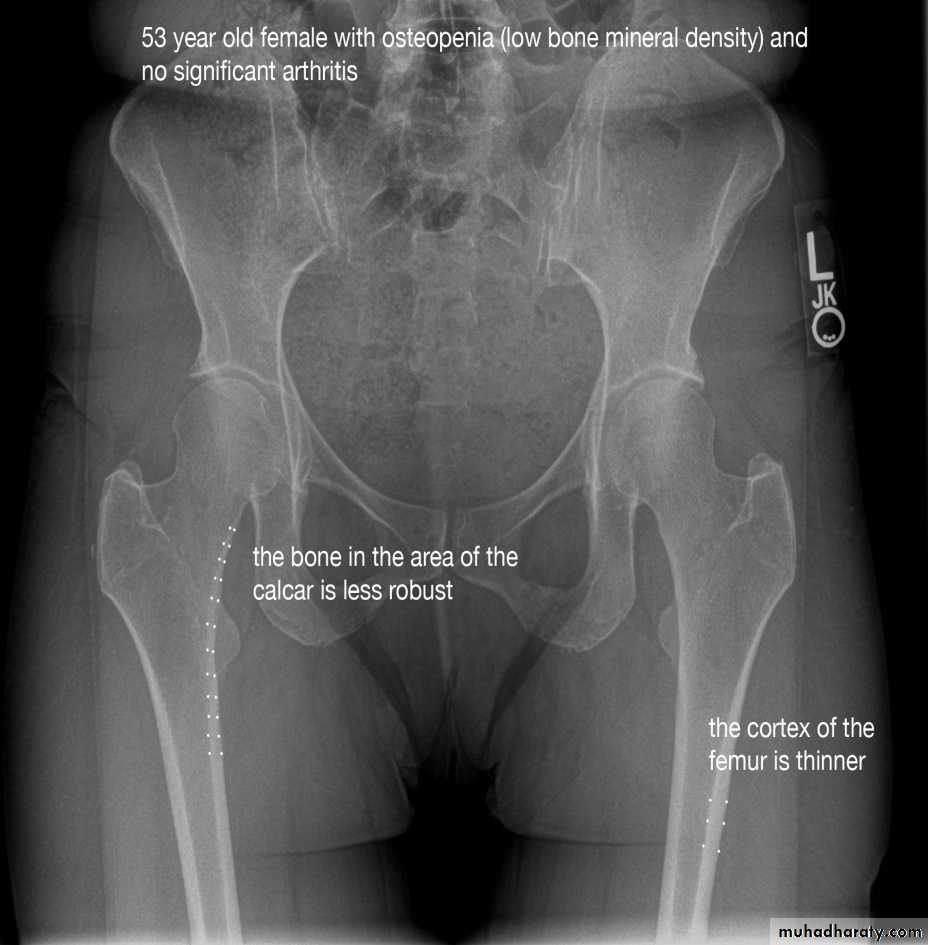

1.decrease in bone density , it can be focal or generalized

5. alteration in trabecular pattern